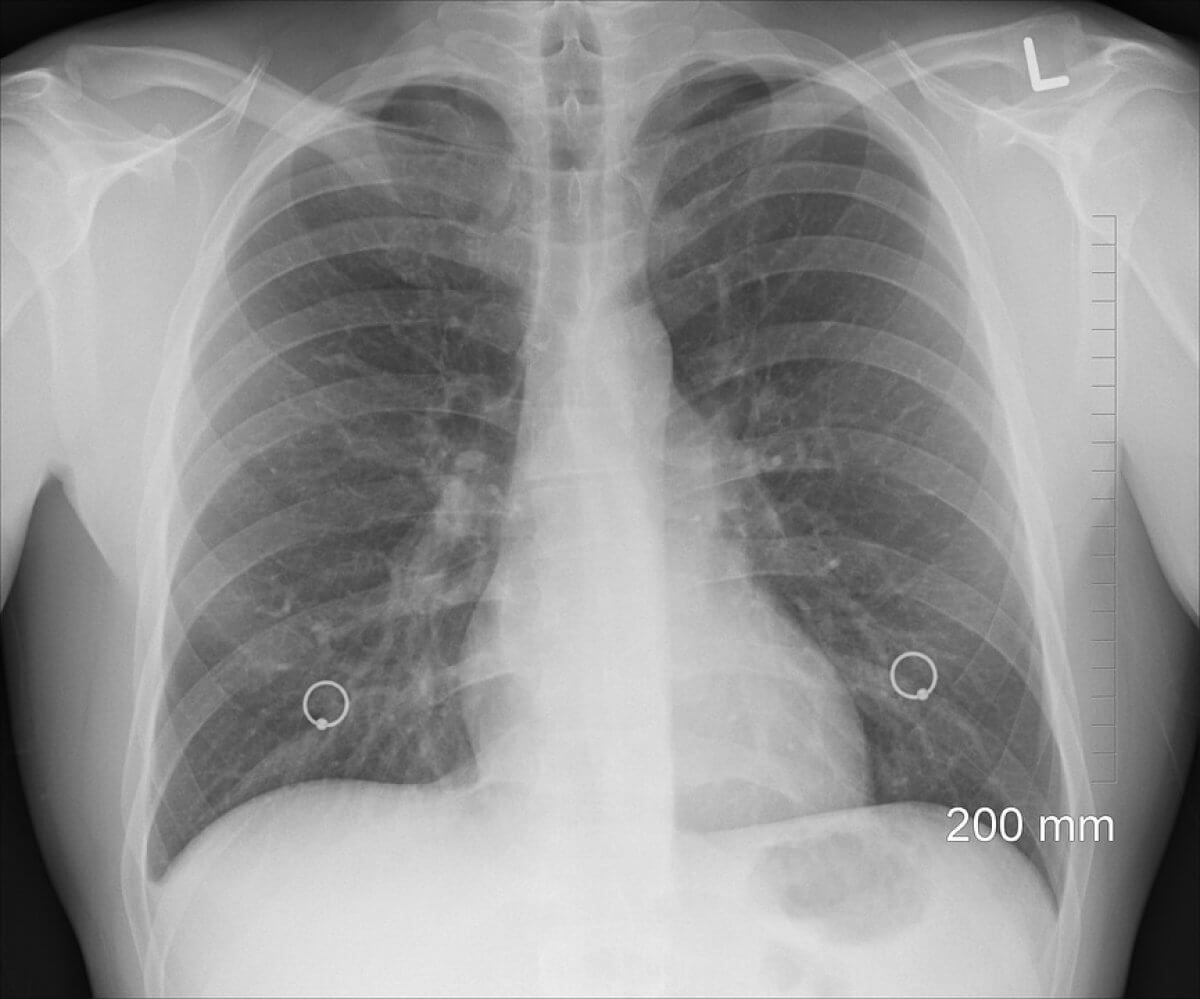

За восемь месяцев 2022 года в Атырауской области выявлен 271 случай заболевания туберкулезом, что ниже прошлогоднего показателя на 9,8%, Но при этом заболеваемость детей выросла на треть.

Заболеваемость детей и подростков является одним из основных индикаторов, определяющих эпидемиологическую ситуацию по туберкулёзу. За восемь месяцев заболеваемость туберкулезом детей выросла на семь случаев, всего – 21 случай, - рассказали в ведомстве.